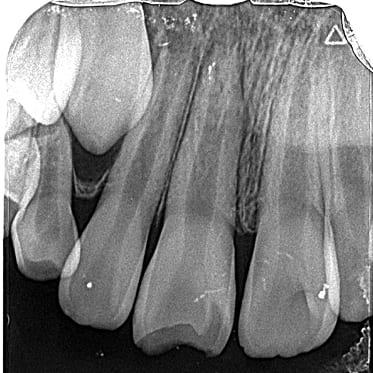

● C4を超え歯根までの虫歯を抜歯、スペースを利用して歯並び全体を整えた症例

藤沢デンタルオフィスの虫歯や破折で抜歯後の部分矯正